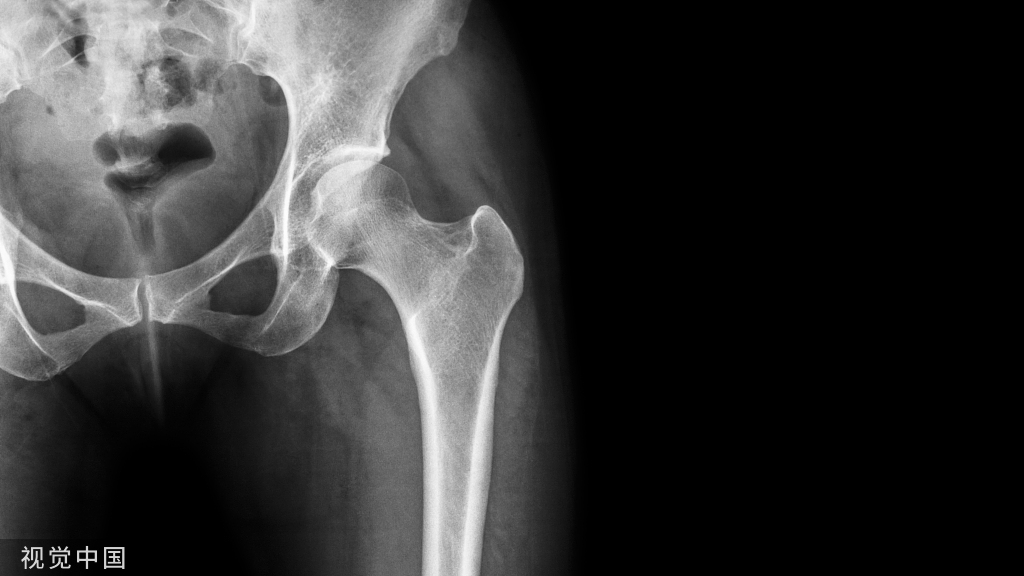

患者男性,19岁,51kg,ASA I级,左侧股骨开放性粉碎性骨折术后,拟行清创,感染髓内钉取出术。入室前未用术前药,常规监测心电图,血压,氧饱和度,脑电图。麻醉诱导平稳,并用地氟醚,阿曲库铵维持麻醉,麻醉中持续吸50%的氧气。患者处于右侧卧位,血流动力学稳定。

髓内钉取出后,手术医师用注射器连接橡皮管向骨髓腔内注射了300mL的 1% H2O2,以便彻底清洗骨髓腔,冲洗过程中可见入口有气泡,未见液体流出, 15min后PetCO2迅速由32降至15 mm Hg,此时血压138/80 mm Hg,心率65 bpm,SpO2维持在97%。

Donatis报道一例16岁少年因股骨干创伤行外科手术。手术过程中,在进行双氧水冲洗伤口时病人突发心跳骤停,由中心静脉导管抽出一连串气泡由此诊断为气栓。尽管心肺复苏取得成功,但病人转归并不理想,病人长期处于植物状态并于8月后死亡。

Shida K报道一例19岁患者行股骨开放性骨折清创术时,用大量双氧水冲洗骨髓腔时发生气体栓塞,但氧饱和度一直在94%以上